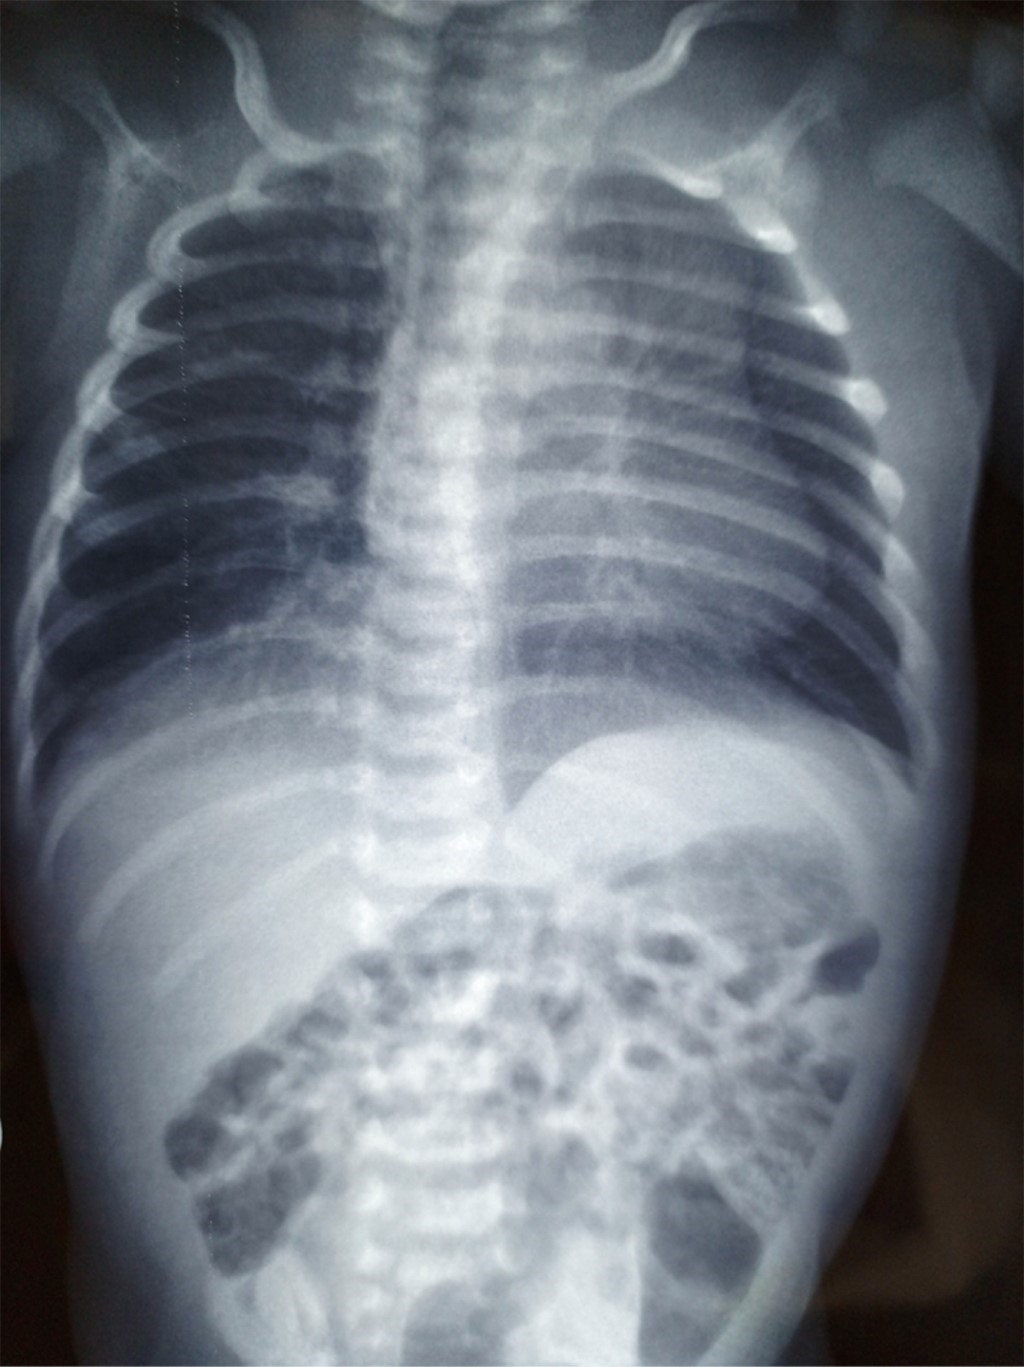

Al nacimiento se identificó malformación a nivel del tórax, con agenesia del pectoral derecho y amastia (Figura 1), así como sindactilia/braquidactilia de la mano derecha (fusión del tercer, cuarto y quinto dedos/anular, dedo del medio y el menique o dedo auricular) (Figura 2). No se detectó alguna otra malformación en el resto de la exploración física. En la radiografía de tórax no evidenciaron alteraciones óseas (Figura 3). Con los datos clínicos y de imagen se concluyó un síndrome de Poland grado I.

Figura 3